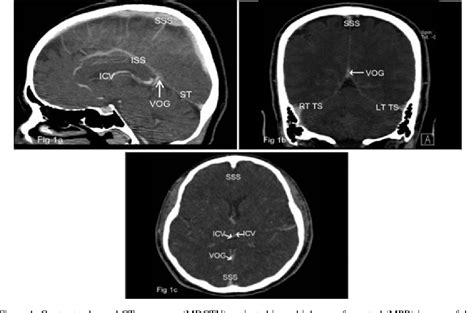

Imaginea de mai sus ilustrează un RMN sagital T1 al regiunii hipofizare, probabil evidențiind o glandă anormal mărită, prin disproporția vizuală în raport cu șaua turcească și conturul convex superior.

2. Semne radiologice pe imagini sagittale T1/T1 cu contrast:

- Contur convex superior – hipofiza mărită prezintă un contur bombat în sus, spre regiunea supraselară. În perioada pubertă sau sarcină, aceasta poate fi fiziologică, dar la adulți nehunorați sugerează adesea adenom sau hiperplazie.

- Volum crescut – hipofiza poate depăși ~9 mm înălțime (femei adulte). În sarcină, poate ajunge până la 12 mm; valori mai mari sunt patologice.

- Captare de contrast:

- Hiperplazie difuză → captare uniformă, dar cu volum mărit.

- Adenoame → captare inegală, cu zone mai puțin intensificate (hipocaptante).

- Hipofizită (inflamatorie) → hipercaptantă, cu prindere accentuată și extinsă local.

- Efecte mecanice de masă:

- Extensie supraselară, compresie a chiasmei optice (risc vizual crescut).

- Extensie paraselară sau remodelare osoasă a șeii turcești.

- Pe secvențele T1 precontrast, lobul posterior (“bright spot”) este hiperatenuat. În glandă mărită (hiperplazie sau adenom), acest semn poate fi modificat sau deplasat.

- RMN-ul dedicat hipofizei include imagini sagittale și coronale T1 cu rezoluție ridicată și FOV (field-of-view) restrâns, cu și fără gadoliniu, plus secvențe dinamice după contrast.